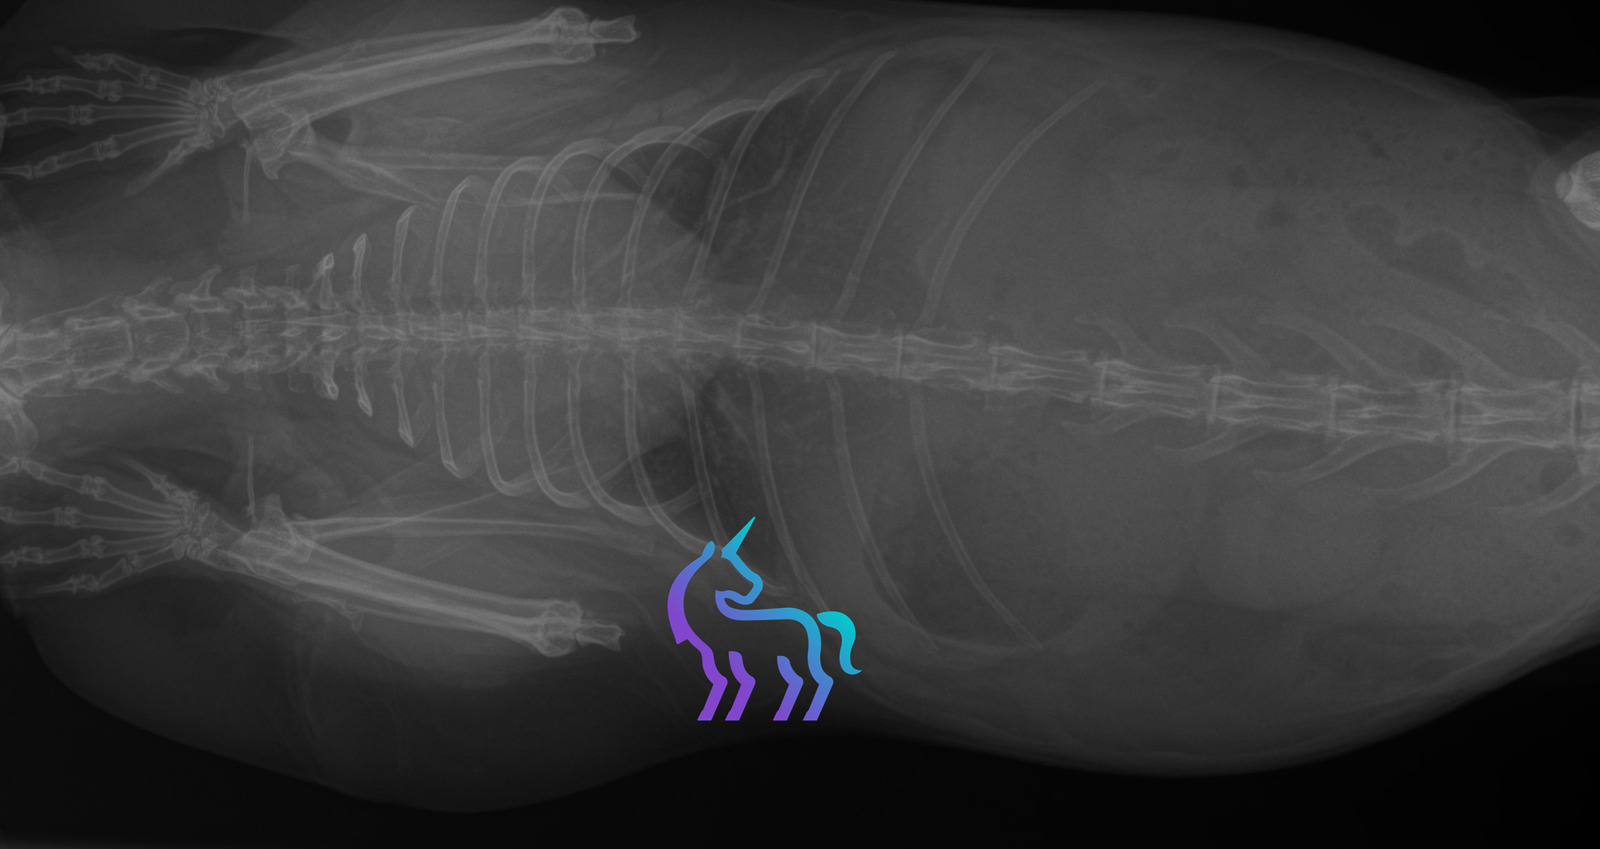

Imagerie thoracique

- Radiographies thoraciques : mise en évidence d’une masse médiastinale craniale, parfois associée à une déviation de la trachée ou à des modifications pulmonaires secondaires.

- Échographie thoracique : permet de caractériser la masse, de rechercher un épanchement pleural et de guider une ponction.

- Scanner (CT) : recommandé pour le bilan d’extension, l’évaluation des rapports anatomiques et la planification d’une chirurgie ou d’une radiothérapie.